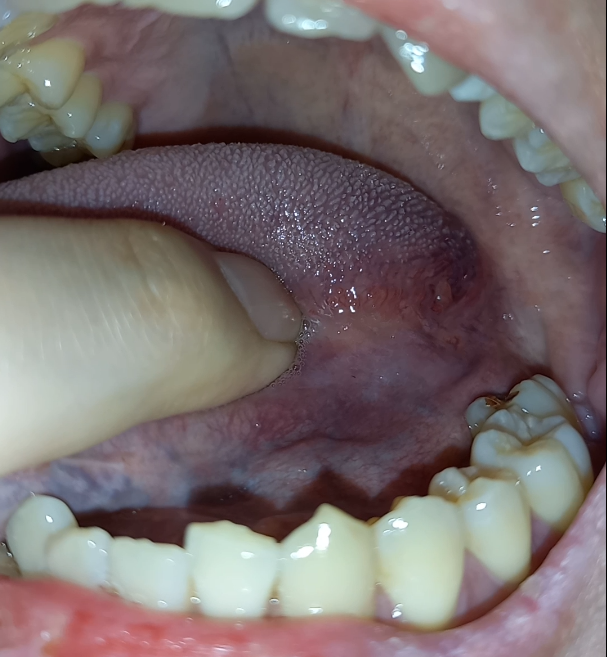

혀 측면 가장 끝쪽에 돌기같은게 나있는걸 발견하게 됐습니다.

혹시나 해서 반대편도 확인해보니 비슷한 돌기가 있더군요.

왼쪽 오른쪽 사진은 첨부해 두겠습니다.

돌기 위에 빨간 부위는 실핏줄같은것처럼 생겼습니다. 혀를 앞으로 당겨오니 보이더라구요. 이것도 양쪽 다 보입니다.

양쪽에 보이는 돌기는 정상적인 구조물인건가요? 아님 치료가 필요한 건가요?

• 2번 째 사진